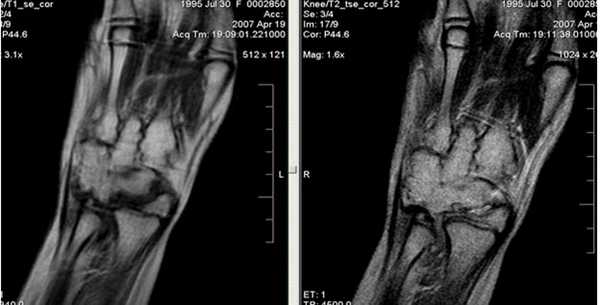

Ревматоидный артрит. Субхондральные эрозии, гипертрофия синовиальной оболочки.

Ревматоидный артрит. Анкилозирование костей запястья, деструкция эпифизов лучевой и локтевой костей.